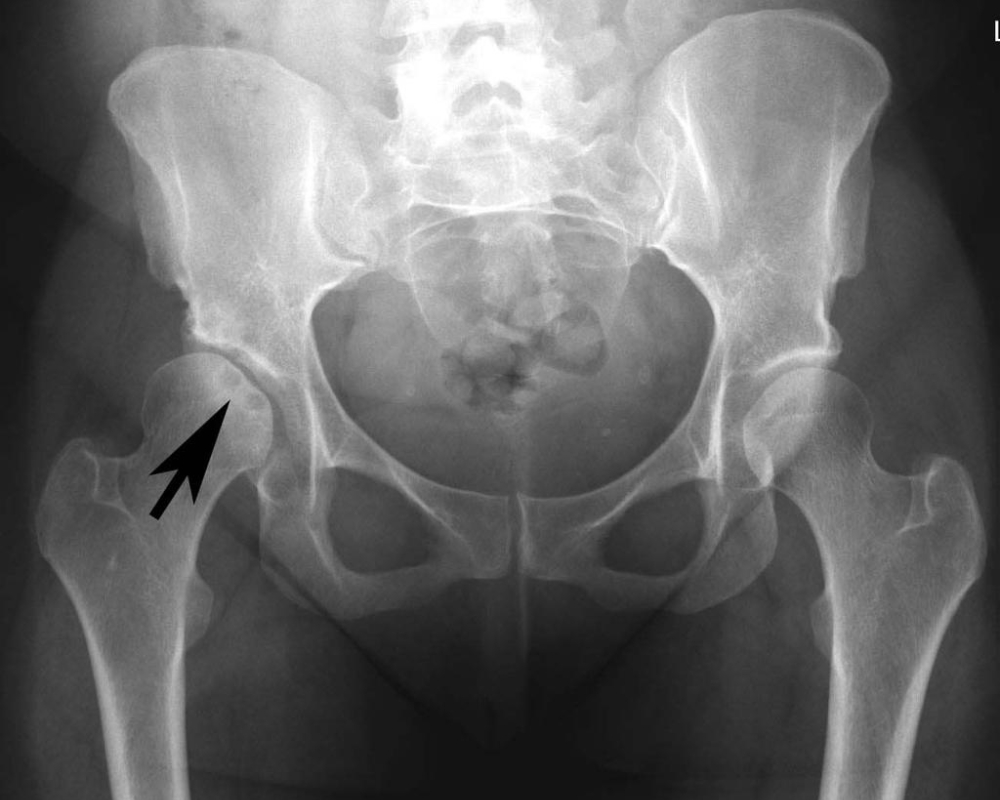

Hình ảnh thoái hóa khớp háng

Để chẩn đoán chính xác thoái hóa khớp háng, sau khi thăm khám, bác sĩ dựa vào các dấu hiệu đau và tiền sử bệnh để đưa ra các chỉ định như X - Quang, CT hoặc MRI cộng hưởng từ để lấy hình ảnh, đánh giá mức độ tổn thương từ cấu trúc khớp háng được chụp.

Phát hiện sớm thoái hóa khớp háng qua các ảnh chụp (tùy vào từng trường hợp và giai đoạn bệnh, bác sĩ sẽ chỉ định phương pháp chụp phù hợp):

- Chụp X - Quang: Thoái hóa khớp háng chụp x-quang thể hiện được hình ảnh khe khớp hẹp, gai xương ở nhiều vị trí, đặc xương dưới sụn ở vùng chịu lực lớn, khuyết xương.

- Chụp CT cắt lớp: Chụp CT cho phép dựng hình ảnh xương 3D để đánh giá chi tiết cấu trúc xương, gai xương, khuyết tật sụn khu trú và sự tổn thương xương dưới sụn.

- Chụp MRI cộng hưởng từ: Được đánh giá là phương pháp tân tiến, giúp bộc lộ rõ các tổn thương trong thoái hóa khớp háng như hẹp khe khớp, xơ xương dưới sụn, gai xương, tạo nang, tràn dịch khớp, chèn ép dây thần kinh…